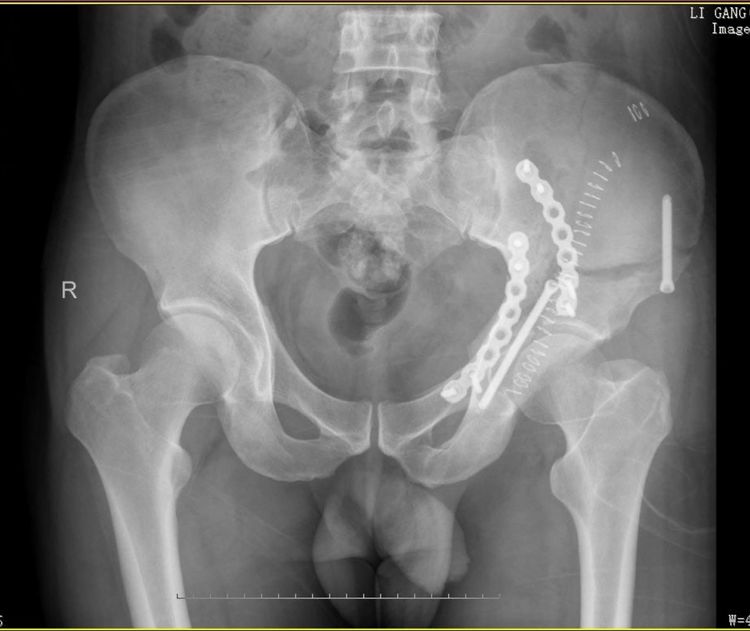

术后前后位

腹直肌外侧入路:近年来,经腹直肌外侧切口入路治疗髋臼并骨盆骨折的手术方式逐渐被广泛应用,该方法与经髂腹股沟入路相比,经腹膜外间隙显露骨盆内侧来治疗复杂骨盆骨折,临床效果明显。切口小,通过后柱通道螺钉稳定后柱结构后,避免了联合后方K-L入路的选择,创伤小,患者术后恢复快,并发症少,满意度高。另外仅用2块钢板和2枚通道螺钉就可以达到稳定固定,极大节约了患者的经济负担。